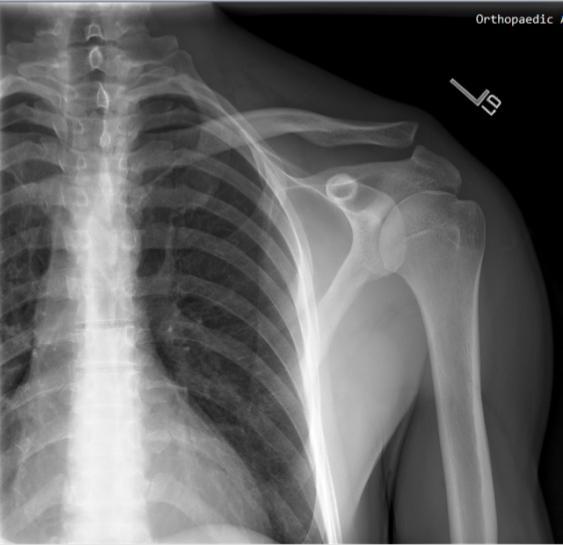

Acromioclavicular Joint Sticking Out. The ac joint is formed by the junction of the lateral clavicle and the acromion process of the scapula and is a gliding, or plane style synovial joint. May be the only finding in type i injuries.

The ligaments should heal by 3 months and at which point a strengthening program may be commenced. Apply it for around 20 to 30 minutes directly to the joint either by using an ice bag. Also labeled are the humeral head (hh), the glenoid, the coracoid process (cor) and the spine of the.

The acromioclavicular ac joint capsule is It is the junction between the acromion (part of the shoulder that forms the highest point of the shoulder) and the clavicle. The acromioclavicular, or ac, joint is a joint in the shoulder where two bones meet.